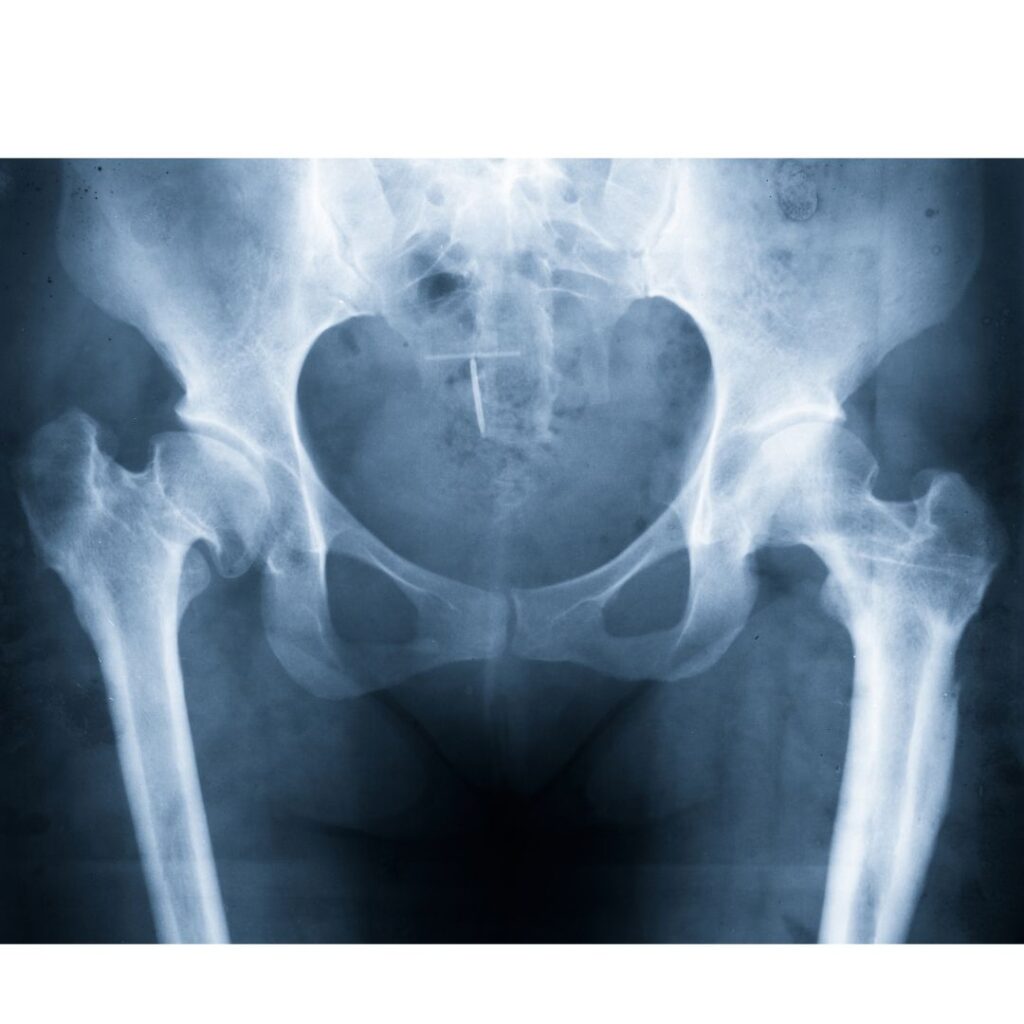

1. Hip Fractures

Hip fractures are common in elderly individuals due to falls and in young individuals due to high-energy trauma.

Types of Hip Fractures

- Femoral Neck Fractures: Located within the capsule; risk of avascular necrosis due to disrupted blood supply.

- Intertrochanteric Fractures: Occur between the greater and lesser trochanters; usually have a good blood supply.

- Subtrochanteric Fractures: Extend below the lesser trochanter; require more complex fixation.

Triage and Management of Hip Fractures

- Stable patients: Urgent orthopedic consultation and imaging (X-ray, CT scan if needed).

- Unstable patients with suspected bleeding: Immediate resuscitation, stabilization, and surgical planning.

- X-rays: First-line imaging for fractures and dislocations.

- CT Scan: Useful for complex fractures and preoperative planning.